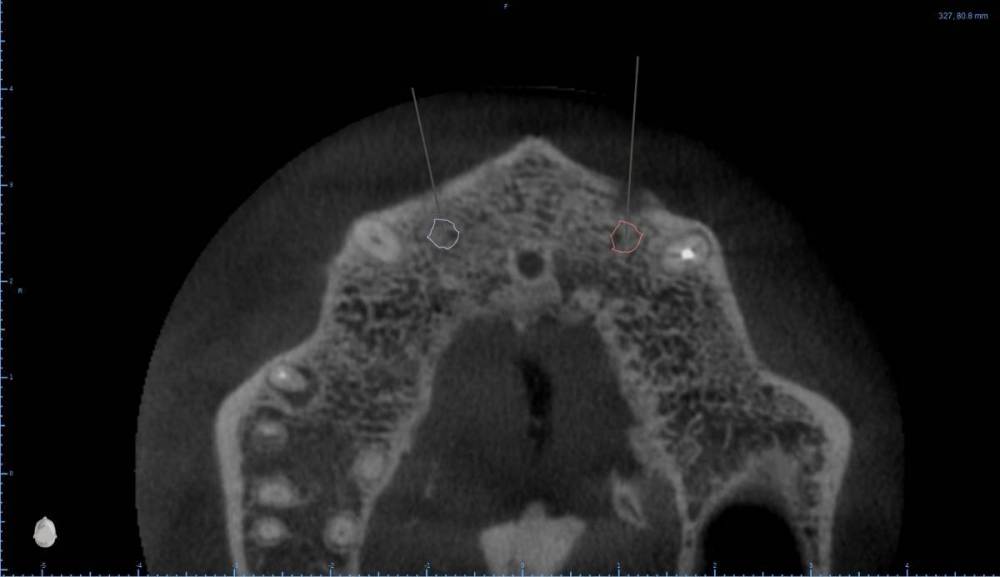

Женька Опубликовано 6 августа, 2022 Поделиться Опубликовано 6 августа, 2022 В общем планируется большая (по крайней мере для меня) работа. Вот такой товарищ у нас. Делали бы НКР в области 2.5з? или поставили бы чисто по кости, а оголённый участок закрыли присыпкой и мембраной? Также вопросы по двойкам имеются. Бугор есть, сразу оговорюсь, правда только с одной стороны. Также не понятно пока "как его правильно готовить" этот бугор, чтобы закрыть такие дефекты вестибулярной пластинки. Скрины постарался нарезать по максимуму. Там ещё будет ортодонтия конечно же. Интрузии, движения всякие и тд) Да, знаю, что планировать без цифрового гипса неправильно, но что имею. Ссылка на комментарий

Irouil Опубликовано 6 августа, 2022 Поделиться Опубликовано 6 августа, 2022 Если будет ортодонтия, то не проще ли вытянуть двойки чтобы вырастить ткани? ИДР тут нужен основательный очень, винты придётся крутить тоже очень длинные В области премоляра не вижу смысла что-то графтить, если хочется чего-то натолкать - можно стружки со сверла упаковать в дефект, но имхо не обязательно. А если сместить винт небно и чуть аннулировать, преп только пилотным и дальше конденсировать... ну Вы поняли 1 Ссылка на комментарий

Женька Опубликовано 12 августа, 2022 Автор Поделиться Опубликовано 12 августа, 2022 (изменено) @TIGER меня размеры дефектов смущают очень сильно. понимаю, что идр лучше, но вариация со смарт билдером по идее тоже должна сработать? Изменено 12 августа, 2022 пользователем Женька Ссылка на комментарий